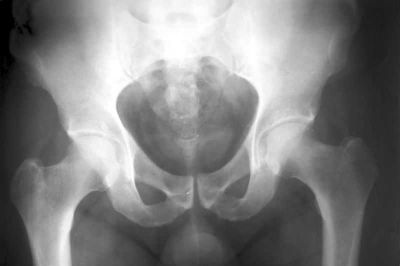

Как сообщается на сайте The Local, норвежец Александр Селвик Венгшол (Alexander Selvik Wengshoel) родился с деформированным бедром и на протяжении нескольких лет передвигался с помощью костылей и инвалидной коляски. Позже он перенес ряд неудачных операций и в возрасте 21 года дал согласие на замену тазобедренного сустава металлическим имплантом.

Осознав, что лучшим выходом из сложившейся ситуации станет замена тазобедренного сустава протезом, Александр в течение года умолял врачей разрешить съемку операции и отдать ему бедренную кость. Поначалу он собирался продемонстрировать кость на выставке, которая должна была состояться в Академии современного искусства в Тромсе, однако неожиданно изменил свои планы - приготовил из собственного бедра ужин, воспользовавшись отсутствием подруги.